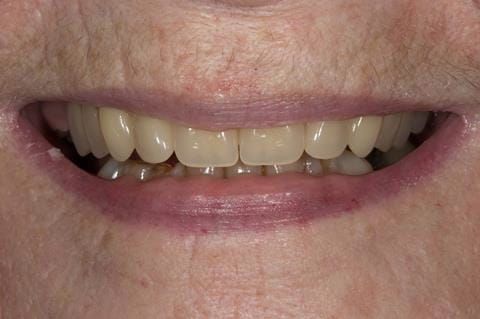

- Cobalt chromium reinforced gasket denture - using a Molloplast B "O" ring to retain and stabilise the denture. This was my professional preference as this was the least invasive and simplest solution to this dental problem. Should the UR7 require removal in the future - an artificial tooth could be added - resulting in a complete denture. The patient would have adapted to the denture fully by this stage and have good neuromuscular control of the prosthesis.

Following consultation and second discussion appointment the patient chose to have option 2 namely, a window denture - maxillary cobalt chromium based partial denture. The clinical situation and treatment process is shown in detail below with photographs. The patient was successfully rehabilitated with this and her quality of life considerably improved. The clinical work was provided by Finlay and the technical work by Rowan.